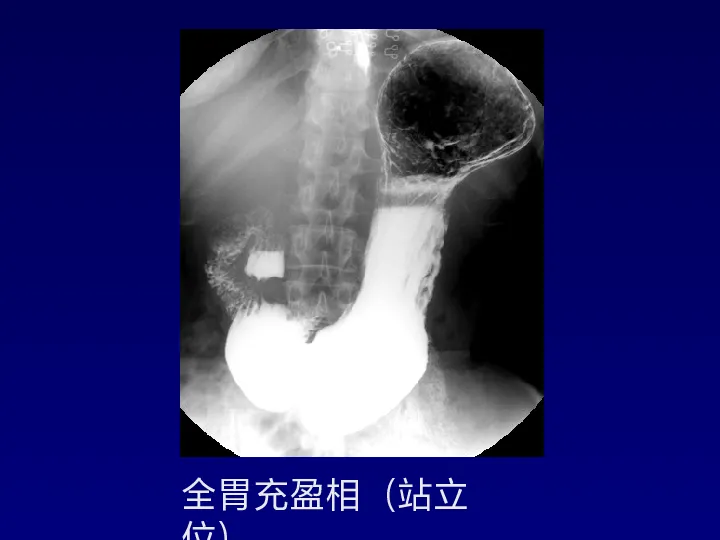

>【影像PPT】胃肠道钡餐检查的操作规范

【影像PPT】胃肠道钡餐检查的操作规范